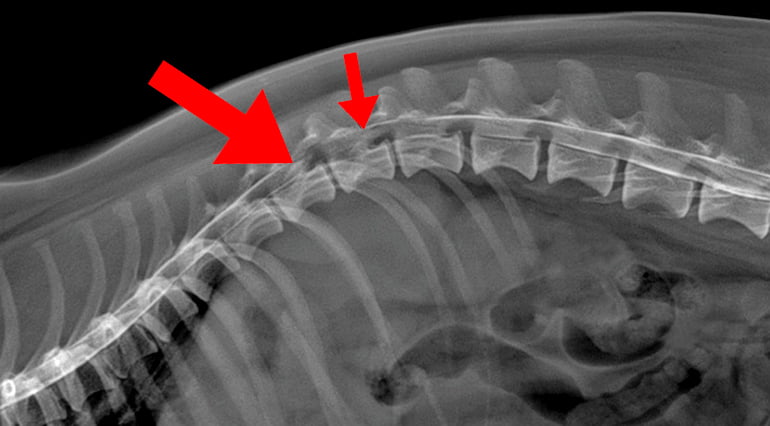

Con la radiografía, en ocasiones se puede observar una disminución del espacio entre las vértebras si existe una hernia discal, pero no siempre se ve claramente. Por ello, la mejor forma para confirmar el diagnóstico es realizar un TAC o una resonancia magnética.